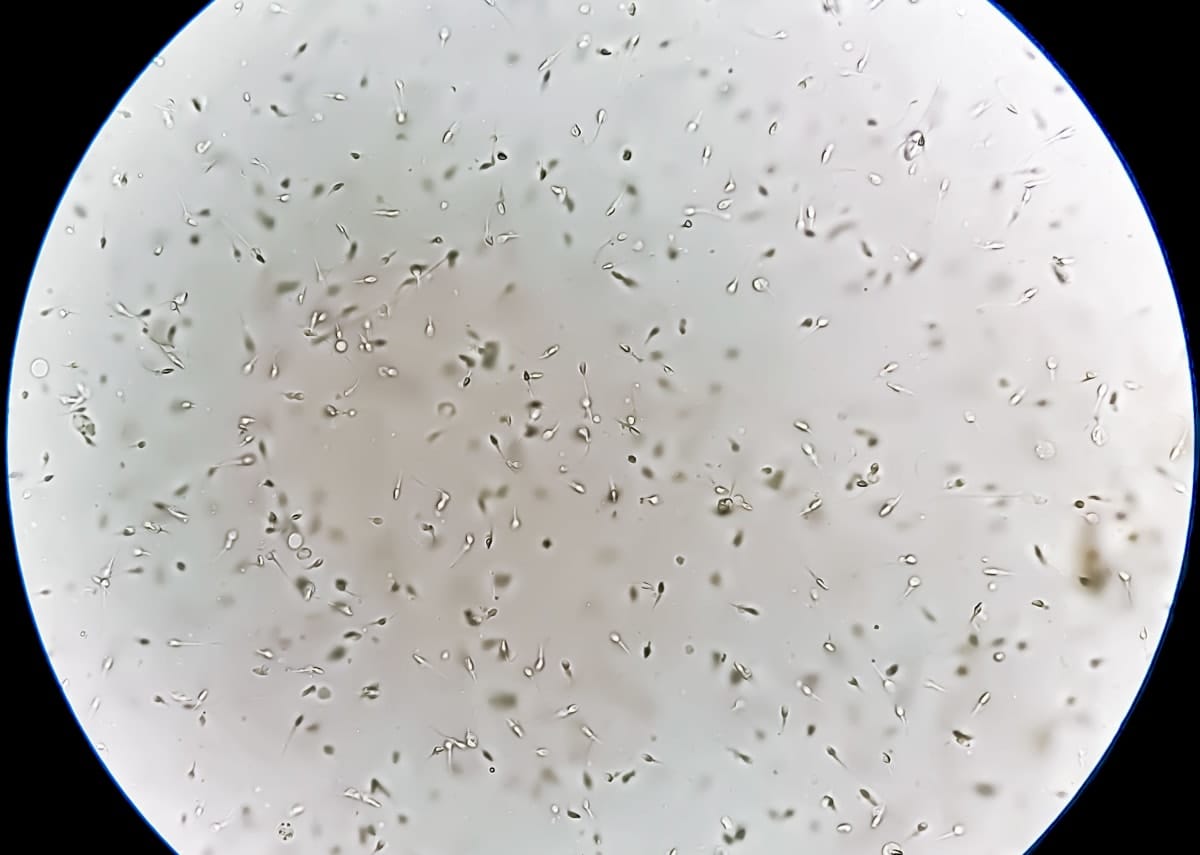

Infertility, the authors write, affects “… one in six couples in Australia, and as high as 70 million couples worldwide. Male factors, including low sperm count, lack of viability, poor motility, abnormal morphology, and/or low DNA integrity contribute to a total of 45% of infertility cases.”

“Motility” here means sperm’s ability to move from one point to another – essential to human reproduction. “Morphology” means size and shape.

They’re flagellated motile cells – basically a cell that has some kind of a hair-type structure, or cilia, that push them to swim.

If you put them in a very confined environment, because of the hydrodynamic interaction between the flow field that forms near that moving filament and the wall, they start to accumulate and swim next to the wall.